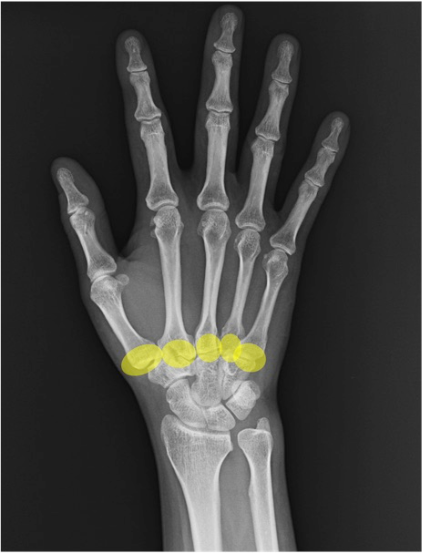

近位手根骨

三角骨(triquetrum)

月状骨(lunate)

舟状骨(scaphoid)